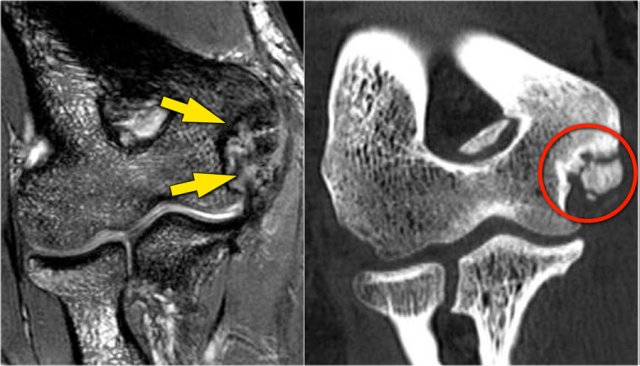

The radiograph is of a 15 year old baseball player with 4 year history of elbow pain and a recent episode of locking.

There is a focal lucency in the capitellum and some fragmntation.

This is typical for a osteochondral lesion of the capitellum and the locking is probably the result of loose bodies.

Continue with the MR...

The MR-arthrogram confirms the osteochondral lesion.

There is gadolinium in between the humerus and the osteochondral lesion which indicates that it is unstable.

If you don't have gadolinium, look for joint fluid undercutting the fragment.

There is a loose body in the posterior recess of the radiocapittelar joint.

Notice also the fragmentation as seen on the axial image.